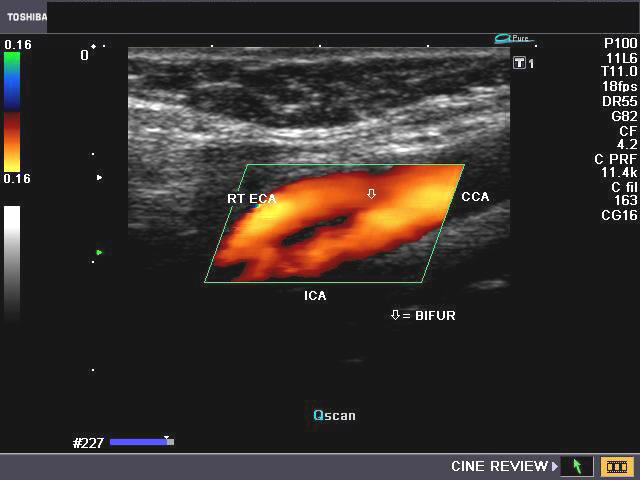

CAROTID Ultrasound examinations of the carotid arteries should include a minimum of the following images. -Longitudinal images of common carotid artery at its most proximal portion, including right ... Read Here